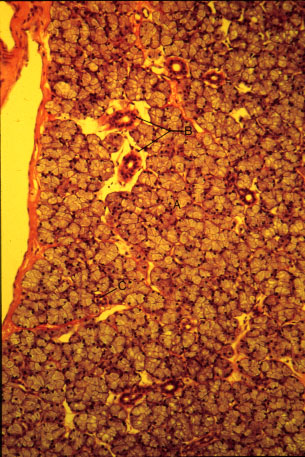

K-slide 56: Higher magnification of slide 55

A. Serous acini

B. Striated duct

C. Intercalated duct